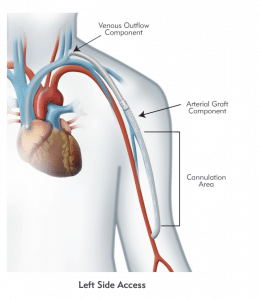

HeRO Graft (Hemodialysis Reliable Outflow) is the ONLY fully subcutaneous AV access solution clinically proven to maintain long-term access for hemodialysis patients with central venous stenosis. HeRO Graft is classified by the FDA as a graft, but differs from a conventional AV graft since it has no venous anastomosis. It consists of two primary components:

The HeRO Graft Arterial Graft Component has a 6mm inner diameter (ID), 7.4mm outer diameter (OD), and is 53cm long, inclusive of the connector. It consists of an ePTFE hemodialysis graft with PTFE beading to provide kink resistance near the proprietary titanium connector. The titanium connector attaches the Arterial Graft Component to the Venous Outflow Component. The Arterial Graft Component is cannulated using standard technique according to KDOQI guidelines.

The HeRO Graft Venous Outflow Component has a 5mm ID, 19F (6.3mm) OD, and is 40cm long. It consists of radiopaque silicone with braided nitinol reinforcement (for kink and crush resistance) and a radiopaque marker band at the distal tip.